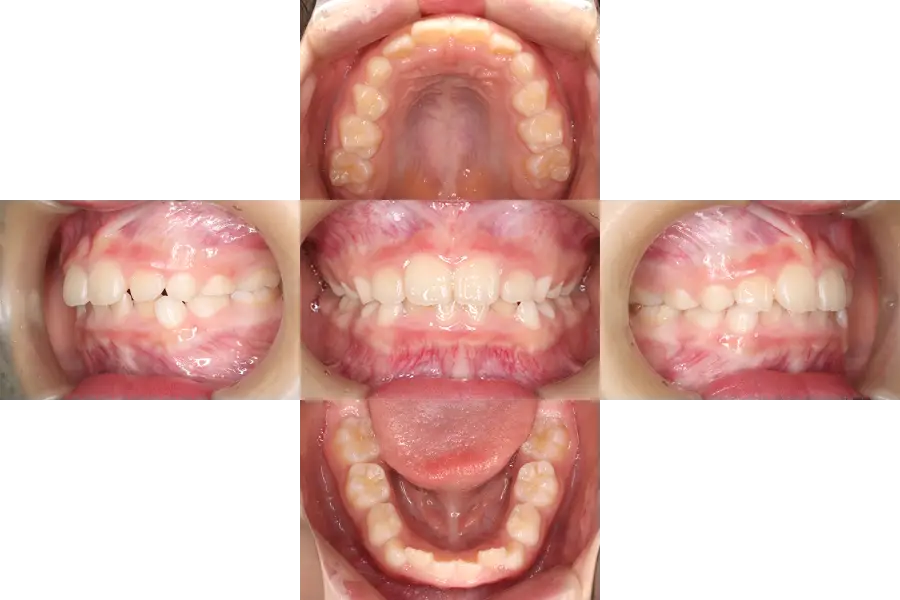

軽度の凸凹の小児矯正治療例

- 主訴

- 前歯の凸凹、永久歯が生える隙間がないと指摘された

- 治療開始年齢

- 10歳

- 診断

- 凸凹、歯の大きさに対して顎が小さい、過蓋咬合

- 難易度

- 軽度

- 使用した装置

- 歯列側方拡大装置、唇側ブラケット装置

- 治療期間

- 約1.0〜1.5年

- 費用(税込)

-

基本料金 399,300円 調整料(約12〜18回) 来院ごと6,600円 総額 478,500円~

- 治療について

初診時には、上顎前突と上下顎前歯の凸凹などが認められました。

検査により、上顎臼歯部の後方移動が可能であると判断し、まずは臼歯部のズレや上顎前突を改善するため、ヘッドギアを装着してもらいました。

ヘッドギアは就寝時も含め、1日10~12時間程度使用してもらいました。

臼歯部のズレが改善したのち、前歯部にブラケット装置を装着し、前歯部の歯並び・咬合を改善しました。

1期治療終了後、永久歯の生え変わりと顎の成長による変化を観察しておりましたが、それらの成長変化が終了した段階(1期治療後5年経過時)でも、良好な歯並び・咬合が得られています。

- 治療のリスク

違和感、痛み、しゃべりにくさ、歯磨きの難しさ、虫歯のリスク増大、矯正装置の脱落、可撤式装置(ヘッドギア)が使用できない可能性、顎の成長や歯・顎の大きさによっては2期治療で小臼歯等の抜歯が必要になる可能性、自費診療。

(生え変わり終了時)